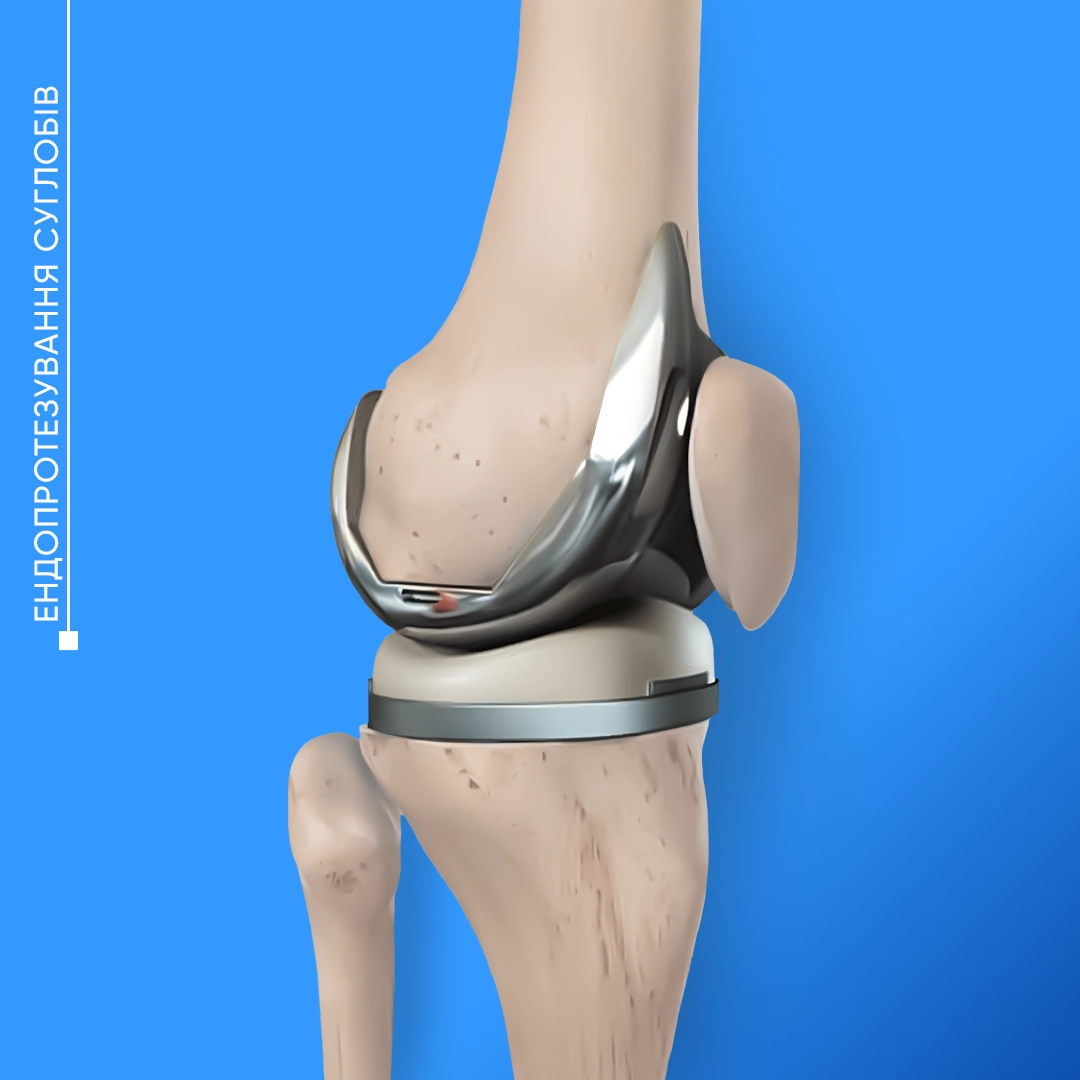

Ендопротезування суглобів — хірургічна операція, яка передбачає заміну суглоба на високотехнологічний протез. Її рекомендують пацієнтам, які страждають від артрозів, артритів, інших захворювань суглобів, які можуть обмежувати рух, викликати біль та ускладнювати повсякденне життя. Також часто оперативне втручання і заміна частини суглоба потрібні після складних травм.

Ендопротезування колінного суглоба — надійний метод відновлення функціональності кінцівки. У випадках запущених остеоартритів та після важких травм встановлення штучного суглоба — порятунок від болю і можливість запобігти повній втраті рухливості коліна.